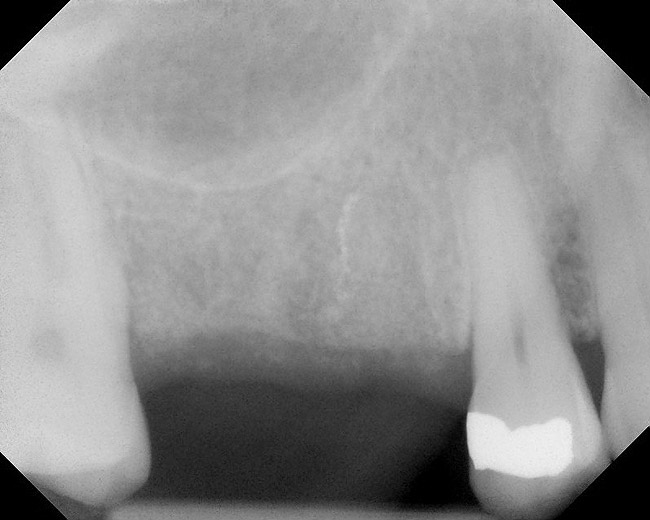

Figure 8  Radiographic confirmation of implant osteointegration into the new bone 14 months after the initial surgery.

Figure 8